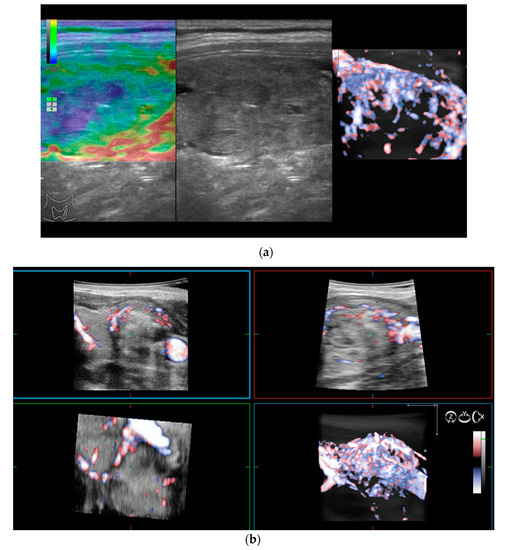

2.3. Volumetric Color Doppler

- Caresio, C.; Caballo, M.; Deandrea, M.; Garberoglio, R.; Mormile, A.; Rossetto, R.; Limone, P.; Molinari, F. Quantitative analysis of thyroid tumors vascularity: A comparison between 3-D contrast-enhanced ultrasound and 3-D Power Doppler on benign and malignant thyroid nodules. Med. Phys. 2018, 45, 3173–3184. [Google Scholar] [CrossRef]

- Lyshchik, A.; Moses, R.; Barnes, S.L.; Higashi, T.; Asato, R.; Miga, M.I.; Gore, J.C.; Fleischer, A.C. Quantitative analysis of tumor vascularity in benign and malignant solid thyroid nodules. J. Ultrasound Med. 2007, 26, 837–846. [Google Scholar] [CrossRef]